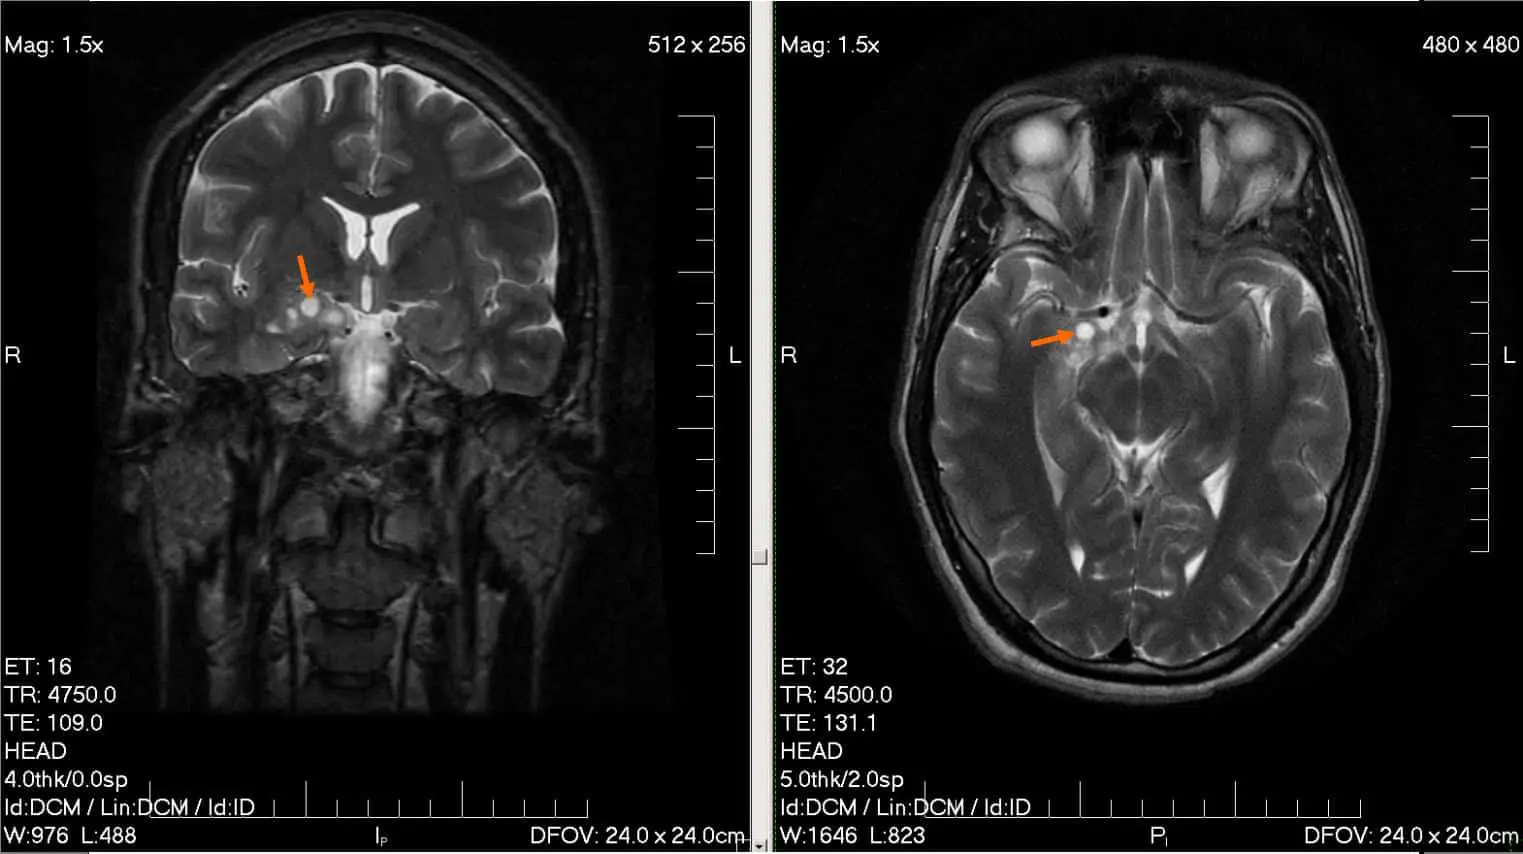

Группа выпускников и исследователей Сеченовского Университета создала уникальное веб-приложение с открытым исходным кодом, размещенным на GitHub. В основе этой разработки — одна из новейших открытых моделей для компьютерного зрения YOLO v11. Для обучения нейросети специалисты собрали и стандартизировали свыше пяти тысяч МРТ-снимков, доступных из открытых источников. Усовершенствованные методы аугментации данных наряду с серией тестов позволили значимо повысить точность: система определяет присутствие и локализацию опухоли с впечатляющей вероятностью 97,1%.

«Разработанное веб-приложение не только обнаруживает опухоли и точно определяет их местоположение на снимках, но и способно предварительно классифицировать тип новообразования», — поясняет Иван Симонович. Система различает такие варианты, как глиомы, менингиомы, аденомы гипофиза и другие опухолевые образования. Уникальность технологии заключается в том, что пользователи, не обладающие специализированными знаниями в области радиологии, получают максимально полную и понятную информацию о характере выявленного патологического процесса — что особенно важно для ранней диагностики и выбора верной тактики лечения.